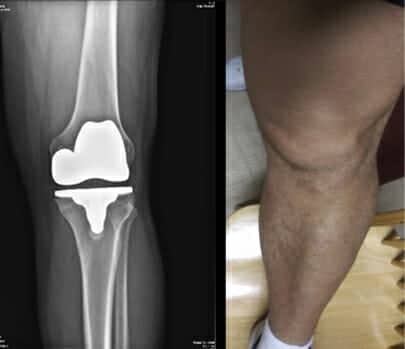

Can The X10 Help You Avoid an MUA (Manipulation Under Anesthesia) after Knee Surgery?

This tool allows you to determine if The X10 Knee Recovery System™ can help you regain your range of motion after surgery. It is used by many as a last resort if they are struggling with knee straightening and bending. To learn more about X10 and avoiding a Manipulation Under Anesthesia you can click here.